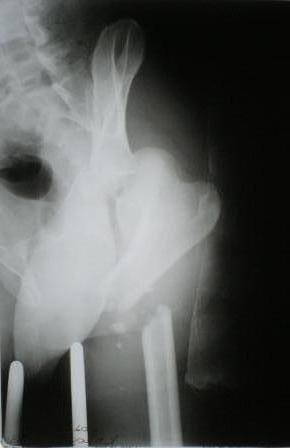

Пациент 33 лет поступил 1.02.08 с диагнозом: Множественная травма. Т-образный перелом свода, перелом заднего края правой вертлужной впадины. Поперечный подвертельный перелом диафиза, подвздошный вывих правого бедра. Поперечный подвертельный перелом диафиза на фоне консолидированного косого перелома в\3 левого бедра в порочном положении. Открытый краевой перелом надколенника правого коленного сустава. Открытый оскольчатый перелом н\челюсти. Закрытый неосложненный перелом V ребра справа. В настоящее время больной компенсирован.

Планируем: в положении больного на спине выполнить БИОС левого бедра ретроградно. После повернуть на левый бок и выполнить БИОС правого бедра антеградно одновременно с Y-образным доступом к вертлужной впадине. После - остеосинтез вертлужной впадины реконструктивными пластинами.